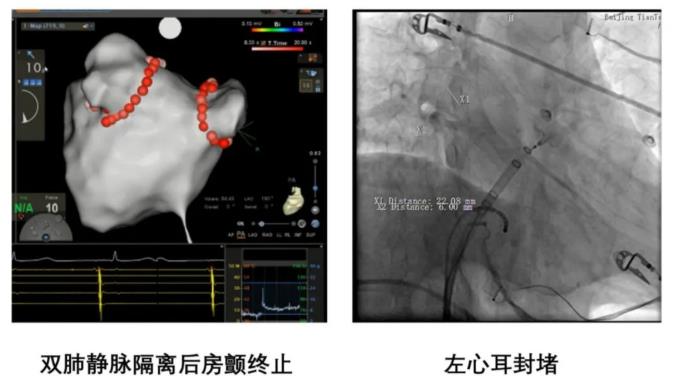

经过精心的术前准备,在麻醉科、超声科、导管室医护人员的全力配合下,术中为王女士进行了双侧肺静脉消融隔离,并将心房最容易形成血栓的左心耳进行了封堵,手术顺利完成。